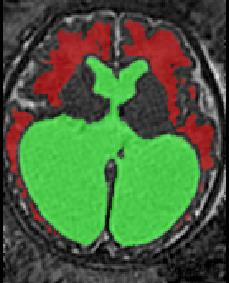

Limiting failures of machine learning systems is of paramount importance for safety-critical applications. In order to improve the robustness of machine learning systems, Distributionally Robust Optimization (DRO) has been proposed as a generalization of Empirical Risk Minimization (ERM). However, its use in deep learning has been severely restricted due to the relative inefficiency of the optimizers available for DRO in comparison to the wide-spread variants of Stochastic Gradient Descent (SGD) optimizers for ERM. We propose SGD with hardness weighted sampling, a principled and efficient optimization method for DRO in machine learning that is particularly suited in the context of deep learning. Similar to a hard example mining strategy in practice, the proposed algorithm is straightforward to implement and computationally as efficient as SGD-based optimizers used for deep learning, requiring minimal overhead computation. In contrast to typical ad hoc hard mining approaches, we prove the convergence of our DRO algorithm for over-parameterized deep learning networks with ReLU activation and a finite number of layers and parameters. Our experiments on fetal brain 3D MRI segmentation and brain tumor segmentation in MRI demonstrate the feasibility and the usefulness of our approach. Using our hardness weighted sampling for training a state-of-the-art deep learning pipeline leads to improved robustness to anatomical variabilities in automatic fetal brain 3D MRI segmentation using deep learning and to improved robustness to the image protocol variations in brain tumor segmentation. Our code is available at https://github.com/LucasFidon/HardnessWeightedSampler.